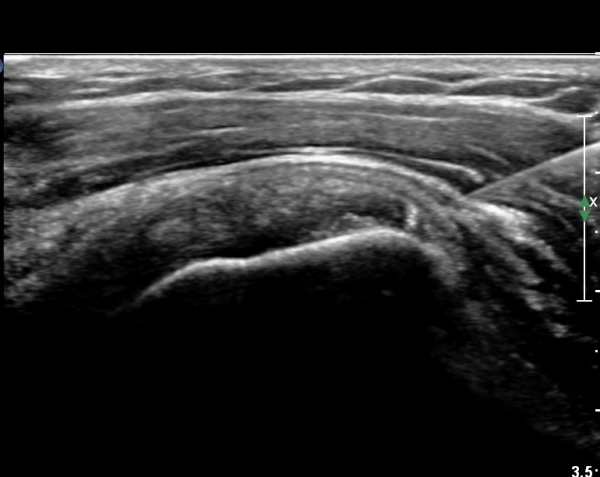

ÀÌµÎ¹Ú±Ù°Ç Á¾´Ü¸é°Ë»ç¿¡¼­ °üÀý³» ¼ö¾×Àú·ù°¡  °üÂûµÈ´Ù(»çÁø 3).